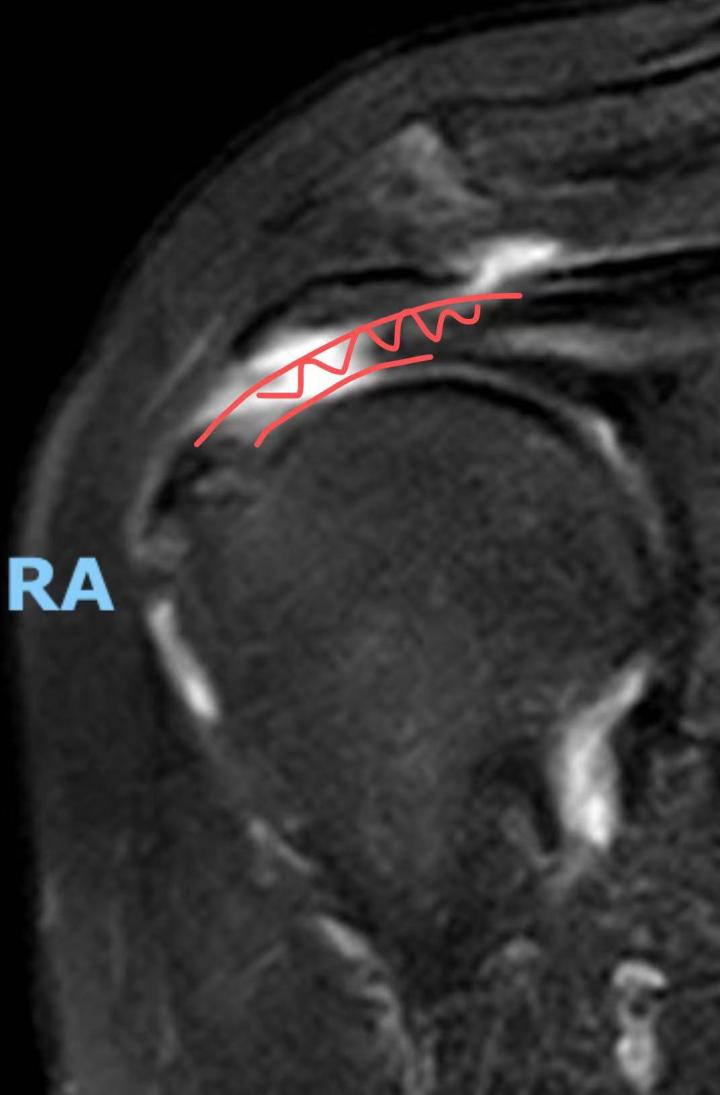

接诊的骨科医师田飞发现吴阿姨的右手几乎抬不起来,综合考虑后,觉得吴阿姨并非是得了 " 肩周炎 " 这么简单,而之后的肩关节磁共振检查也证实了他的猜想——吴阿姨是严重的肩袖撕裂。

图注:白色区域显示肌腱断裂

简单来说,是吴阿姨肩关节里的肌腱断了,而她勤劳的用力锻炼使得肌腱断裂的情况更加严重。田飞医师通过微创手术,使用特制的锚钉和超强缝线,将吴阿姨断裂的肌腱拉回原位缝合并加固。术后,吴阿姨的关节痛终于消失,右臂也渐渐恢复活动能力。